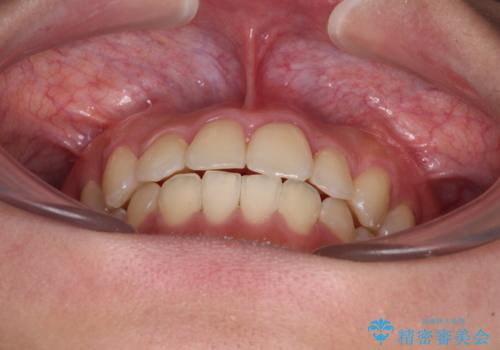

前歯のクロスバイトを短期間で解消 目立たないワイヤー矯正

- 前歯のクロスバイトを治したいとのことで来院された患者様です。

できる限り楽して、短期間で治したいとのことで、ワイヤー装置にて矯正治療を行うこととしました。